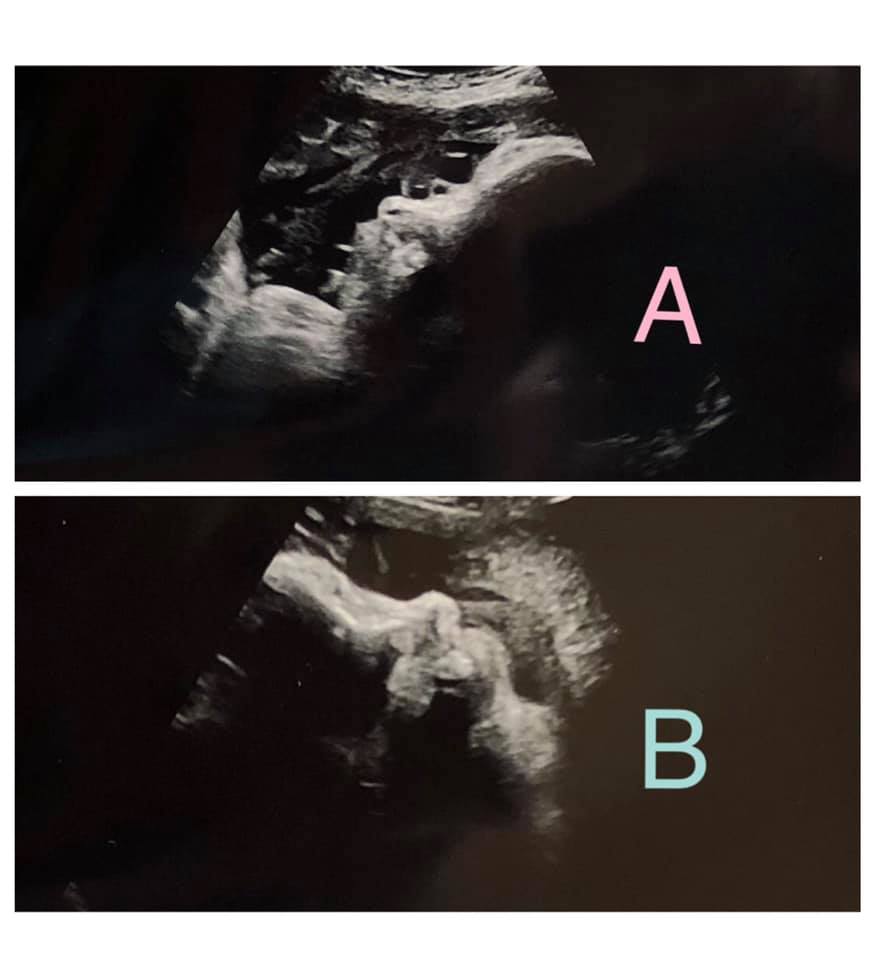

- Ultrasound Photos at 36 Weeks Pregnant With Twins

Ultrasound Photos at 36 Weeks Pregnant With Twins